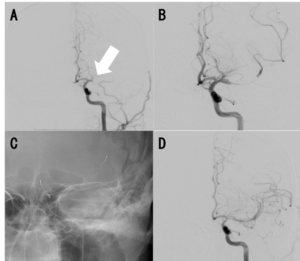

最近、虚血性心疾患と同様に超急性期脳梗塞の一部でもカテーテル治療が施行されるようになりました。当科には脳神経血管内治療学会の専門医が在籍しており、脳神経外科と協力して超急性期脳梗塞の血行再建治療を施行しています。症例数は徐々に増えており、2019年度は血栓回収療法が16件でした。